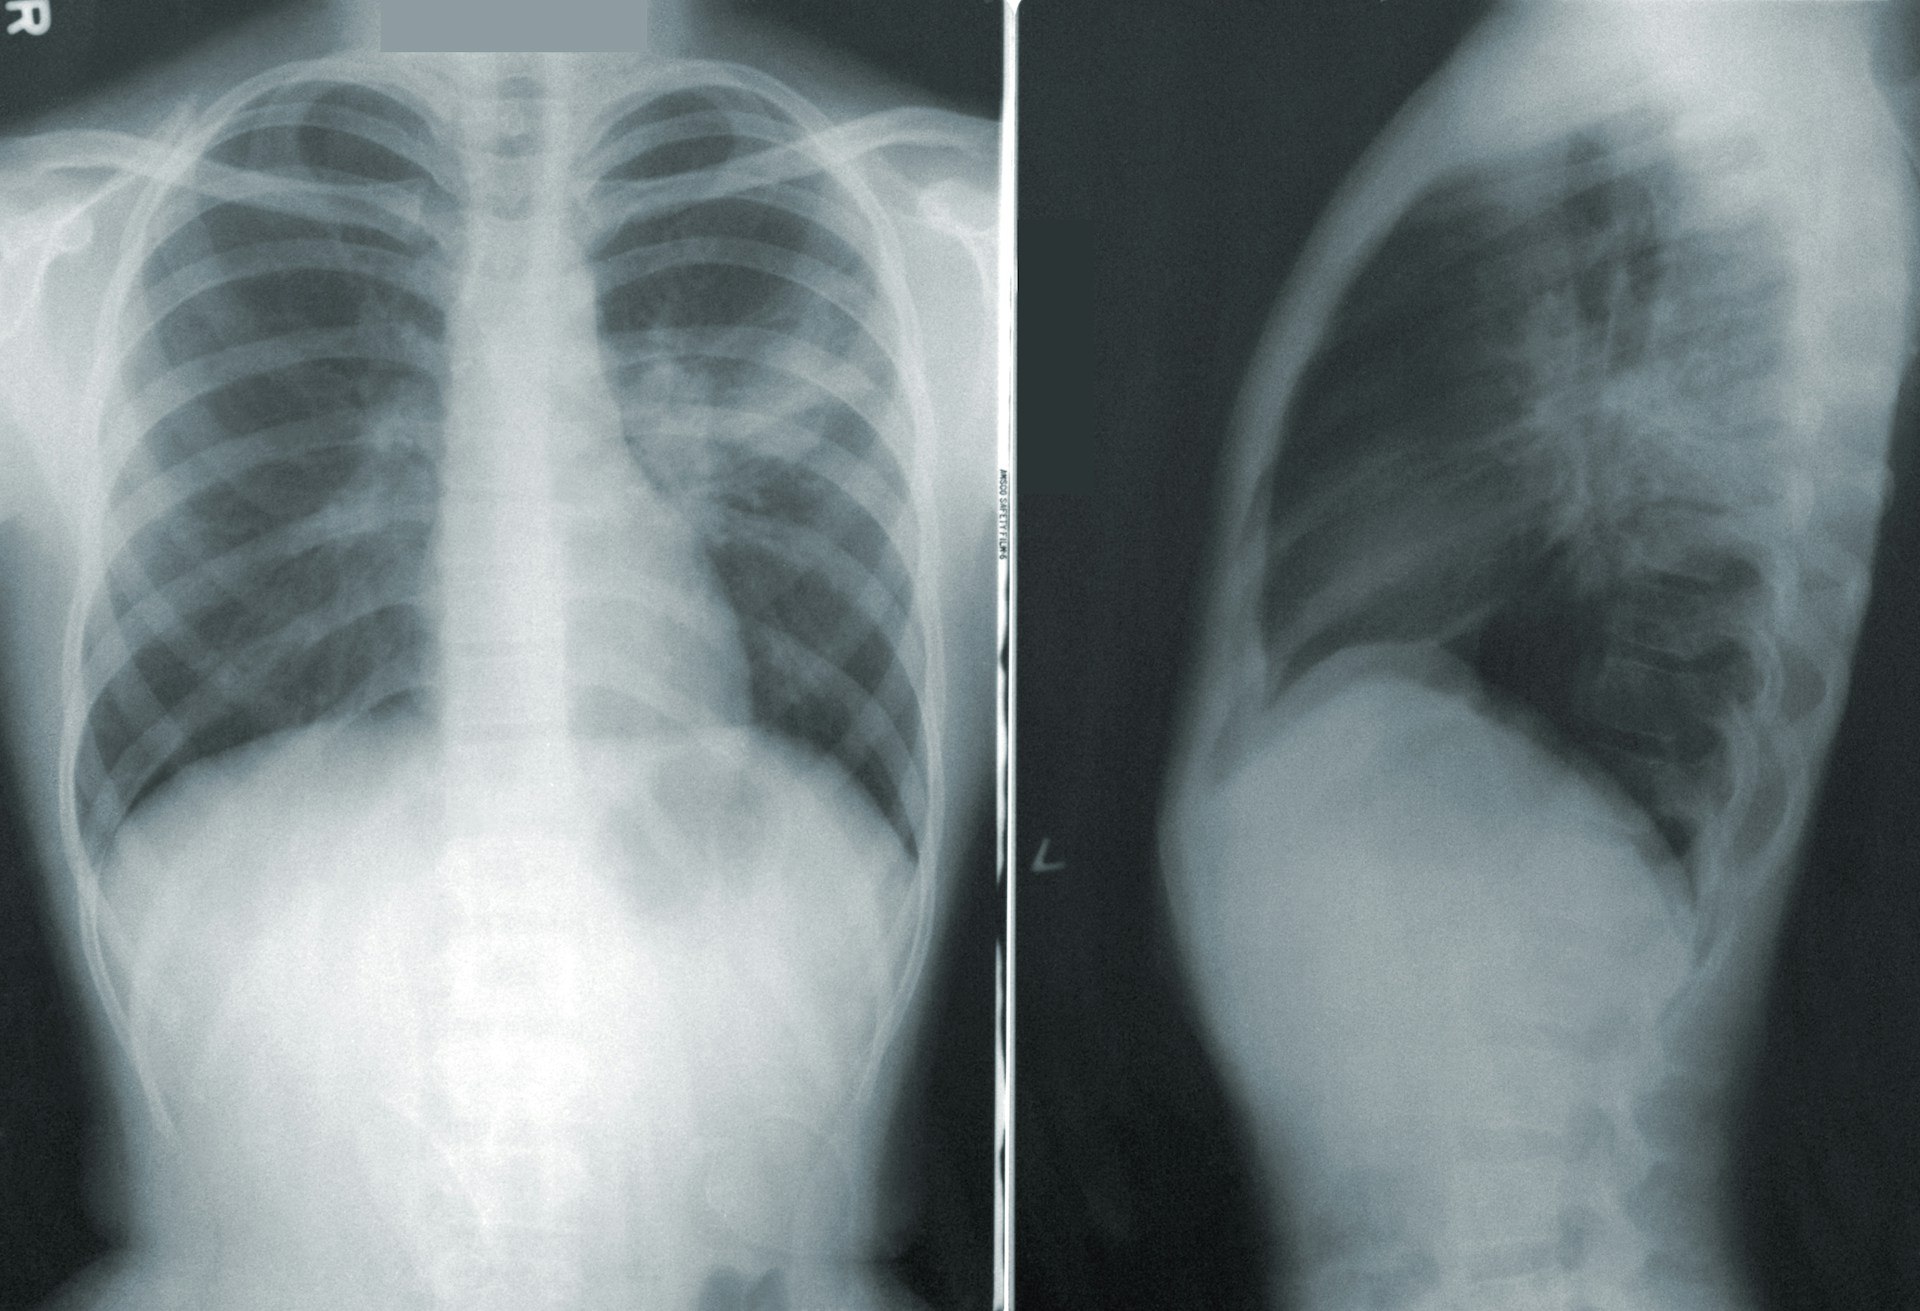

По словам доктора медицинских наук Заура Шугушева, у пациентов, страдающих от нее, стремительно меняется легочная ткань. Все это происходит из-за воспаления, которое вызвано вдыханием токсических веществ, травмами или инфекционными заболеваниями.

В первую очередь EVALI способна вызвать синдром острой дыхательной недостаточности (ARDS). Врачи Ирина Окольникова и Алексей Хухрев предупреждают, что смертность в процентных показателях достаточно высока - от 30 до 50.

При данном синдроме легкие перестают насыщать кровь кислородом. Такое состояние требует подключения человека к искусственной вентиляции легких.

Они во многом похожи на коронавирусную инфекцию. Пациенты чаще всего жалуются на общую слабость, повышенную температуру, кашель и одышку. Однако, в отличие от COVID-19, у данного заболевания одним из первых симптомов является нарушение пищеварительной системы.

Выявить патологические изменения можно после проведения компьютерной томографии.